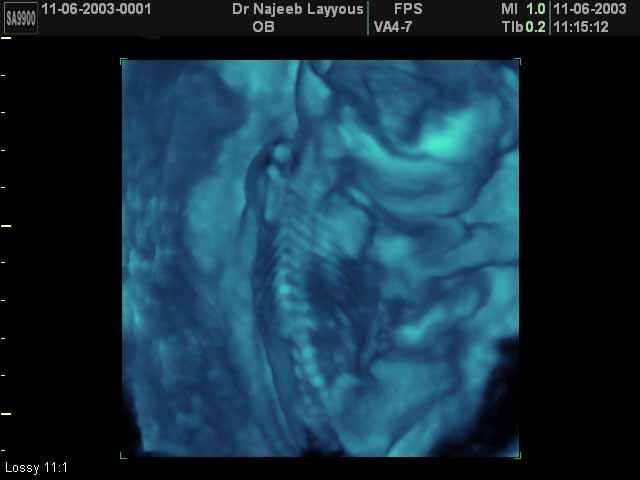

- صور للهيكل العظمي للجنين

صور للهيكل العظمي للجنين بجهاز الالتراساوند ثلاثي الأبعاد | الدكتور نجيب ليوس